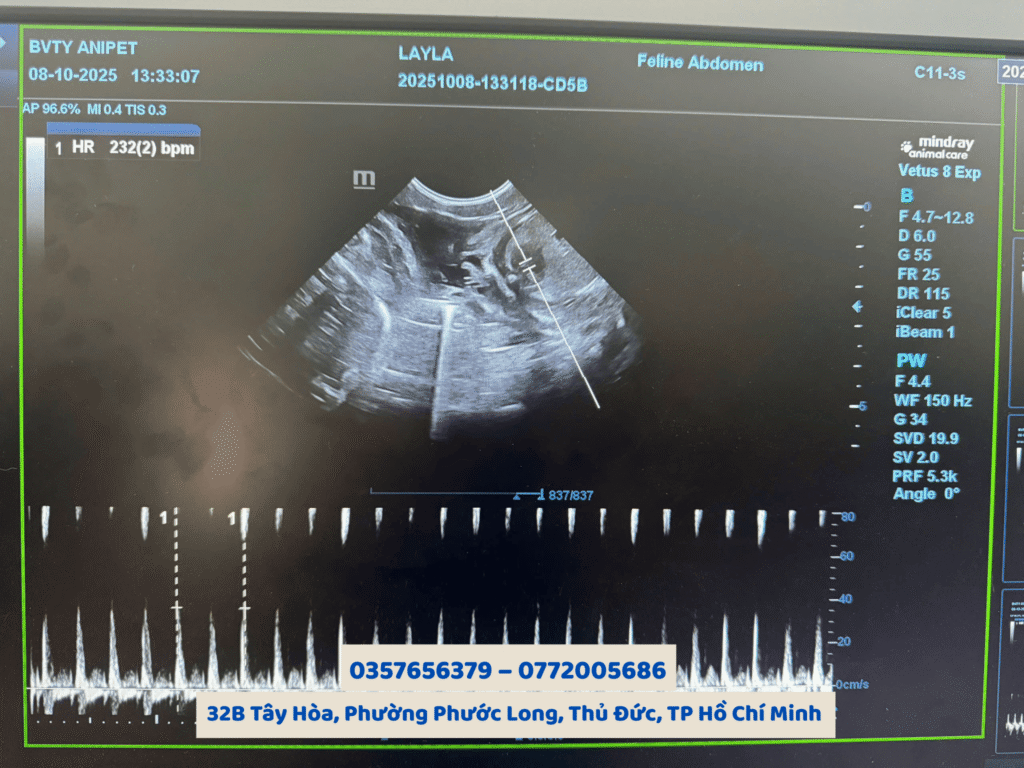

Tại Bệnh viện Thú y AniPet, quy trình siêu âm được thực hiện bằng thiết bị hiện đại, đảm bảo hình ảnh rõ nét và chẩn đoán chính xác, giúp chủ nuôi yên tâm chăm sóc đúng cách khi thú cưng mang bầu

Tại Bệnh viện Thú y AniPet, dịch vụ siêu âm thai cho chó mèo được thực hiện bởi đội ngũ bác sĩ thú y nhiều kinh nghiệm cùng hệ thống máy siêu âm kỹ thuật số hiện đại. Hình ảnh hiển thị rõ ràng, giúp bác sĩ dễ dàng nhận diện số lượng thai, vị trí và nhịp tim của từng bé con trong bụng chó mèo mẹ.

Việc siêu âm thai cho chó mèo định kỳ còn giúp theo dõi sự phát triển của thai nhi, đánh giá tình trạng nhau thai, nước ối, tim thai và phát hiện sớm các bất thường nếu có.